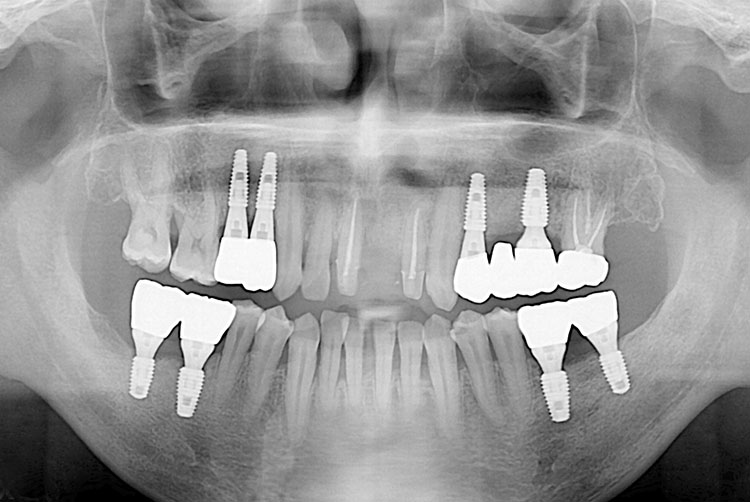

치료후 : 2019-06-26

세종치과는 많은 환자와 다양한 케이스를 바탕으로 항상 편안한 임플란트 수술을 제공하고자 노력하고,

오래동안 튼튼히 쓸 수 있는 임플란트 수술을 가장 큰 목표로 삼고 있습니다